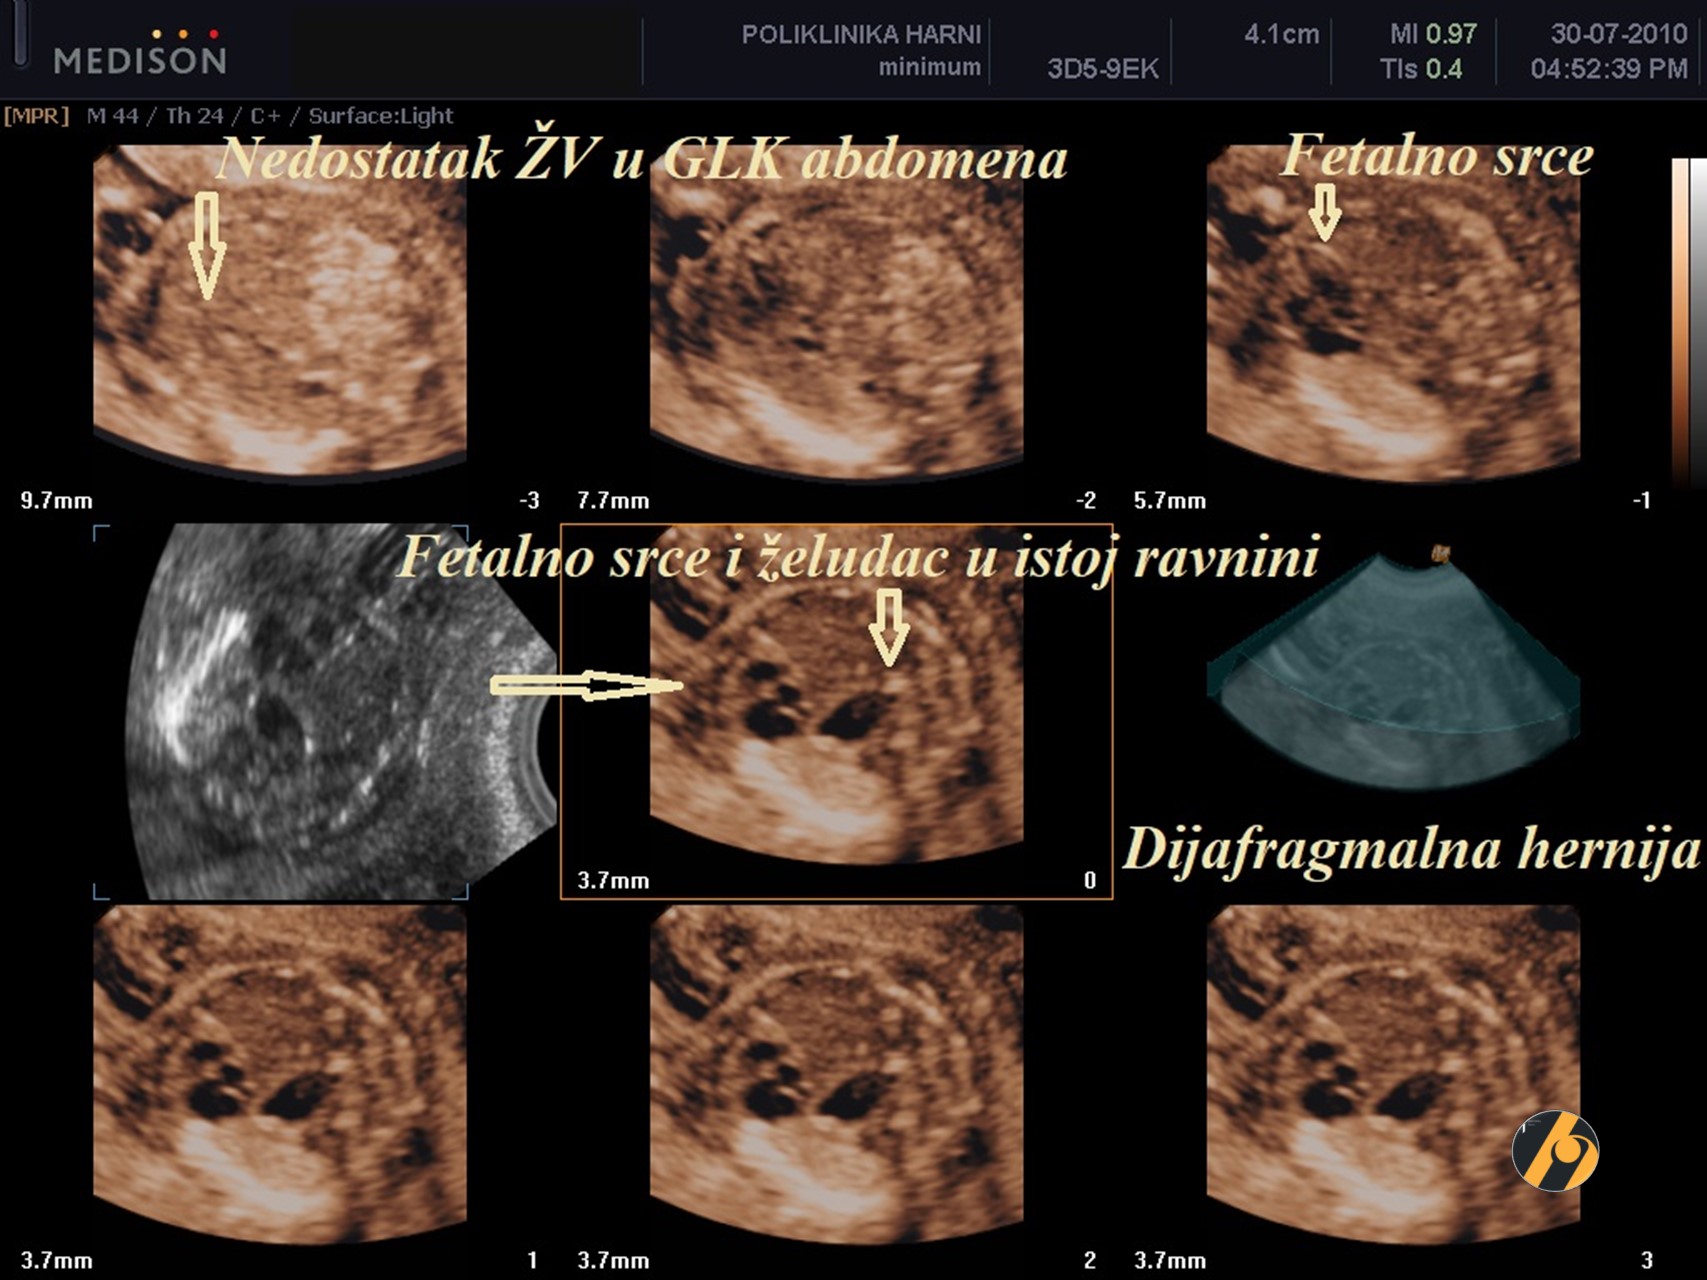

Učestalost dijafragmalne hernije na porođaju iznosi oko 1 na 4.000, a stanje je obično sporadično. Prevalencija kromosomskih oštećenja, uglavnom trisomije 18, je oko 20%.

Povećan nuhalni nabor nalazi se u oko 40% fetusa s dijafragmalnom hernijom, a kod takvih fetusa povećava se rizik od smrti novorođenčadi uslijed plućne hipoplazije. U slučajevima kada je dijafragmalna hernija povezana s dobrom prognozom, intratorakalna hernijacija utrobe kreće od drugog ili trećeg tromjesečja trudnoće, a u takvim je slučajevima veličina nuhalnog nabora normalna.

Slika prikazuje dijafragmalnu herniju dijagnosticiranu u 14. tjednu trudnoće zajedno s aplazijom radijusa i ventrikularnim septalnim defektom. Kariotipizacija nije rađen po želji roditelja, trudnoća je dovršena spontanim pobačajem u 18. tjednu.